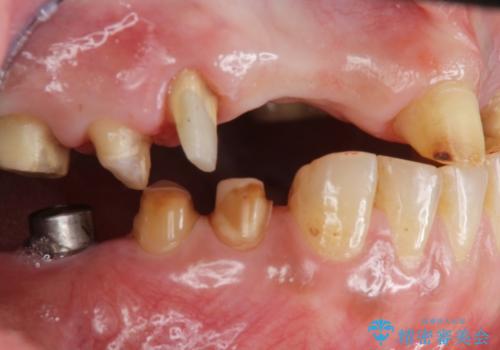

- 痛くて噛めない、これまでだましだまし治療をしてきたがこれを機にすべてきっちりと治したい、口の中の悩みを解決したいと来院されました。

抜歯や歯周病治療、欠損補綴を含め、全顎的な治療を計画・提案します。

口腔内に歯の破折や歯周病、虫歯、欠損など複数の問題が存在する場合局所的に問題を解決していくのではなく全顎的な治療を行っていくことで長期的な予後を見込むことができます。